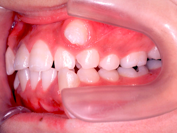

(注) この患者さんの治療の詳細は、院長の治療例の「叢生」(ここをクリック)で詳しく解説しておりますので、治療の方法や期間、治療費、リスク等はそちらを参照してください。